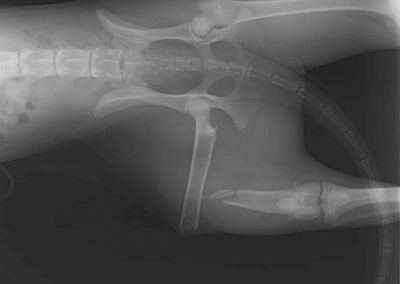

GALERÍA TRAUMATOLOGÍA CANINA

Algunas de las lesiones más frecuentes son las fracturas óseas, las luxaciones articulares, las roturas de ligamentos, los esguinces, las hernias discales, la displasia de cadera o de codo, la osteoartritis o la artrosis.

Estas lesiones pueden provocar dolor, inflamación, cojera, rigidez, pérdida de movilidad, deformidad o incluso parálisis en los perros afectados.

Además, dispone de los medios técnicos necesarios para realizar pruebas diagnósticas como radiografías, ecografías, resonancias magnéticas o artroscopias, que permiten visualizar el estado de los tejidos afectados y determinar el grado de la lesión.